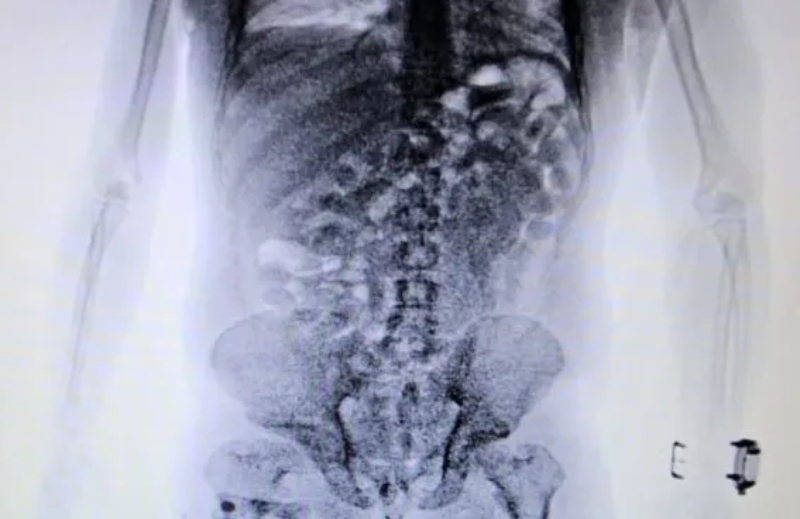

En el Aeropuerto Internacional de Ezeiza, agentes especializados de la Dirección General de Aduanas desarticularon un intento de contrabando de cocaína hacia Europa: descubrieron que un ciudadano brasilero llevaba 84 cápsulas de cocaína en su cuerpo.

Sin embargo, los agentes no encontraron nada. Las dudas persistían y, en medio de los controles, el ciudadano brasileño no logró explicar el motivo del viaje ni quien había comprado el pasaje aéreo. Es por eso que decidieron utilizar otro método de control: el body scan. Las imágenes confirmaron las sospechas del personal aduanero dado que mostraban cuerpos extraños.

Según señala el organismo de control en un comunicado, “ante la posibilidad de que se tratase de un método de ocultamiento de estupefacientes, se internó al pasajero en un centro médico y lograron confirmar que había ingerido cápsulas con droga. En total eran 84 y contenían 1134 gramos de cocaína que en el país de destino se podría vender a USD 51 mil”.